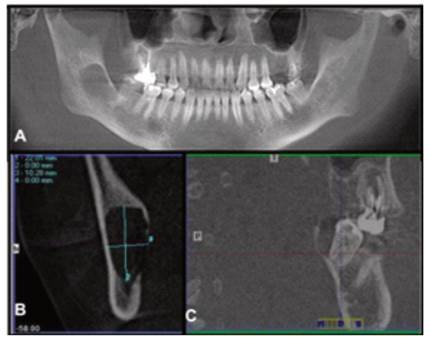

En la radiografía panorámica se observa amplia lesión de aproximadamente 5 x 4 cm de diámetro, de contenido radiolúcido, unilocular de límites definidos, bordes corticalizados, proyectado desde distal de segmento radicular de pieza 4.7, extendiéndose en dirección cefálica hasta aproximadamente la mitad de rama mandibular, comprometiendo en su crecimiento a la pieza 4.7, región posterior de cuerpo mandibular, ángulo y rama mandibular derecha. Se observa ausencia de pieza 4.8 y leve desplazamiento caudal de canal mandibular.

En la Tomografía Computarizada de Cone Beam, en su reconstrucción panorámica (Figura 2A) se corrobora lesión hipodensa, extensa, de bordes definidos y corticalizados, que compromete segmento radicular de pieza 4.7. La reconstrucción transversal muestra lesión de 22.01 x 10.28 mm de tamaño, forma ovalada, expansión de corticales y severo adelgazamiento con perforación de cortical lingual (Figura 2B). En la reconstrucción sagital se evidencia exposición de región distal y palatina de pieza 4.7 con reabsorción ósea alveolar completa de esta región, corroborando además leve desplazamiento de canal mandibular en dirección caudal (Figura 2C).